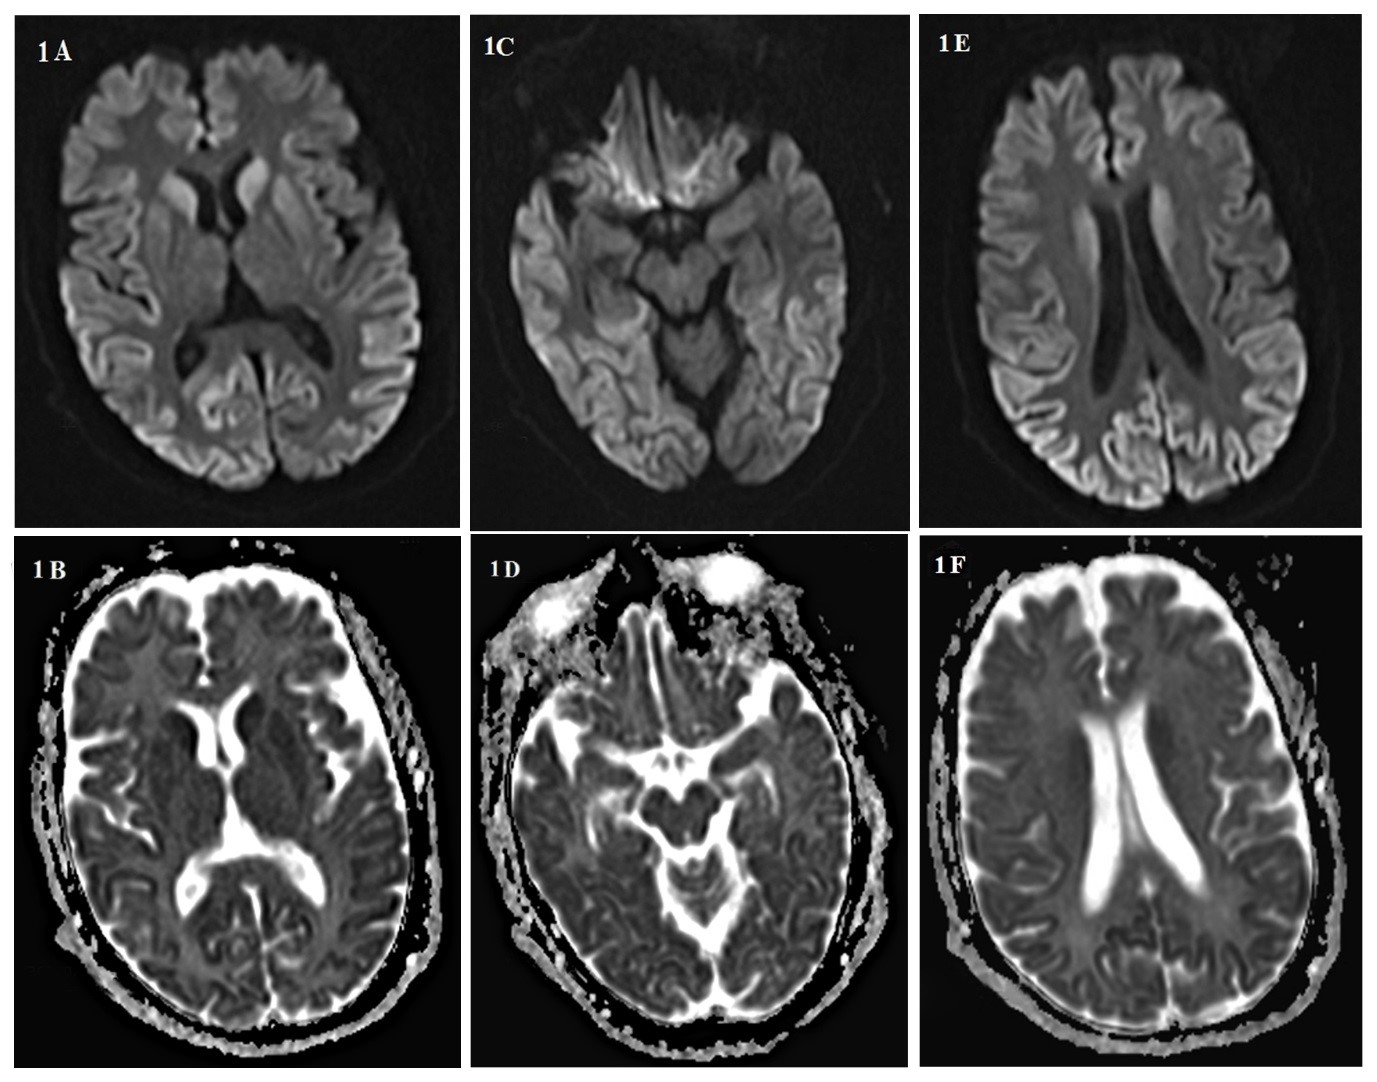

Background: Creutzfeldt-Jakob disease (CJD) is a progressive and fatal prion disease in human and its annual incidence is estimated one per million. Sporadic form of CJD is the most common form of the disease that involved 85% of cases. Case Report: We presented two cases of CJD with the different clinical presentation; a 58-year-old woman who referred with amnesia, depression and a 59-year-old woman with ataxia as her chief complaint. Based on the findings and roled-out the other differential diagnosis, the CJD was confirmed. Both of them died before 12 months after diagnosis. Conclusion: Although CJD is a rare disease with different clinical manifestation, it is considered as one the differential diagnosis of progressive dementia.[GMJ.2019;8:e1357]Â